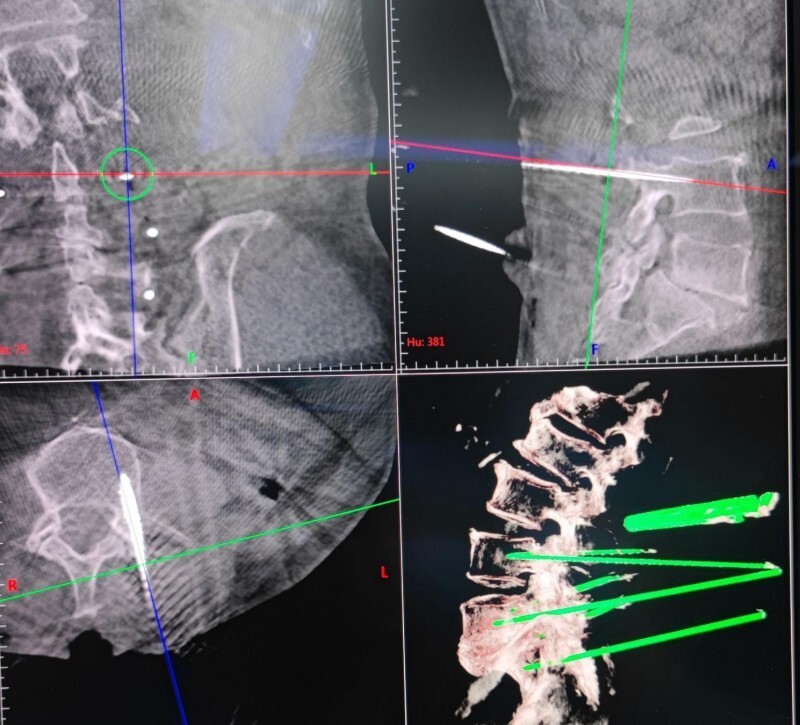

术中精细规划,经过机器人的辅助定位精确

“天玑”骨科机器人是我国自主研发的第三代国产骨科手术辅助机器人,由“光学跟踪系统"、“机械手臂”及“操作平台”三个部分组成,可以帮助骨科医生精准、高效的建立骨性通道,在微创下完成各种复杂的骨科手术,临床精度可达到0.1mm级别。目前应用于四肢及骨盆骨折、脊柱(颈椎、胸椎、腰椎、骶椎)手术。使用“天玑”机器人能够将患者解剖空间位置信息与影像信息融合,可对手术进行可视化规划,利用机械手臂实现空间定位,并对机械臂的精度实时监控,在保证安全的前提下真正做到“智能化”、“微创化”,真正做到“知行合一”。